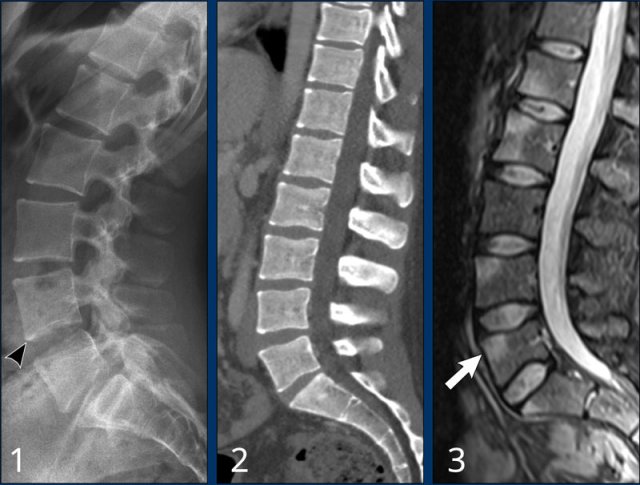

Early stage ankylosing spondylitis Early stage ankylosing spondylitis

Enthesitis

Inflammation of the enthesis is one of the hallmarks of SpA.

The earliest sign of ankylosing spondylitis is edema at the enthesis, which is only visible on MRI (white arrow).

In a later stage sclerosis will present as shiny corners on X-rays or CT.

Finally syndesmophytes are formed along these enthesis (see next images).

Images

Three different patients with typical features of early stage ankylosing spondylitis:

1. Shiny corners of the anterior border of vertebrae where the enthesis is located. Squaring of the vertebral bodies is seen.

2. Another patient with squaring and shiny corners of the vertebral bodies on CT.

3. This patient has edema at the enthesis of vertebral bodies, visible on sag STIR.